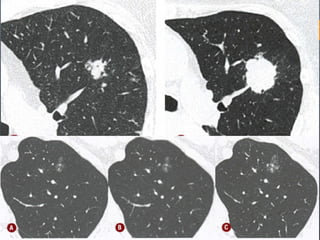

O documento discute vários conceitos radiológicos incluindo consolidação, atelectasia, nódulos, pseudocavidades e padrões intersticiais, fornecendo definições, sinais e diagnósticos diferenciais para cada tópico. Ele também discute a redução da atenuação pulmonar e fornece um link para mais informações.